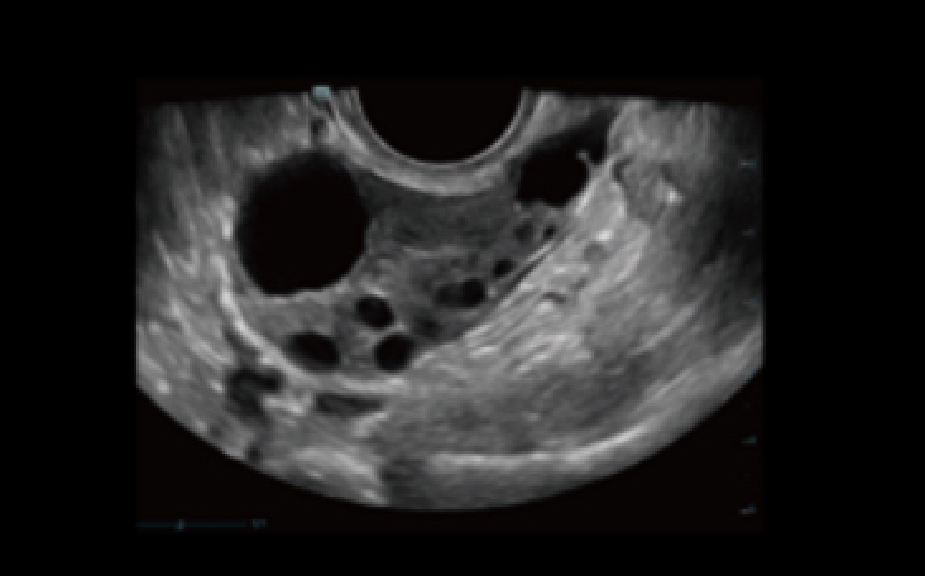

Pre-pregnancy

Efficient quantification for endometrium

Pre-pregnancy